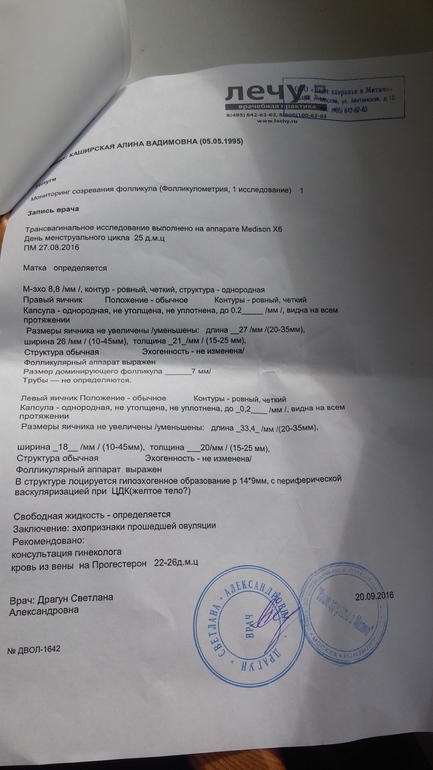

Девочки,сходила я значит на фолликулометрию и чет расстроилась...О подтвердили. Предыстория : сегодня у меня 25ДЦ и 5ДПО. Все в норме,жт есть,но его немного! Врач сказал сдать кровь на прогик-уже сдала,завтра заберу результаты. Теперь я так переживаю,что проблемы с прогиком и пролет в этом месяце...единственно что врач сказал,что ДПО прошло немного и возможно из-за этого жт нет в нужном кол-ве. Девочки,поддержите ((((неужели это пролет...p.s анализы (под кат)

подожди расстраиваться!!!!все хорошо-еще не понятно.жт можно подрастить с помощью дюфа.....если прогик не обнадежит да и детке есть где крепиться ...правда не вижу эндометрий какой

Эндометрий 8,8 :) сказали здесь все хорошо...вот только жт...